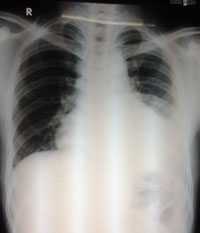

CTMTP: Bạch cầu tăng 13.000/mm3, bạch cầu ái toan chiếm ưu thế 11%, bạch cầu đa nhân trung tính 70%; chỉ số CRP: 47 mg/L (bình thường < 3); men gan AST: 88 U/L, ALT: 100 U/L, GGT: 100 U/L; men tim CK-MB, Troponin T: Âm tính; X-quang phôi: bóng tim lớn nhẹ, tràn dịch màng phổi phía bên (T); siêu âm tim: màng ngoài tim Echo kém, dày 3 - 5 mm; siêu âm bụng: Gan lách bình thường, ghi nhận TDMP (T), bề dày lớp dịch 37 mm.

Sau 3 ngày điều trị bệnh nhân vẫn còn sốt, đau ngực tăng, đau cả ngực (P) và (T). X-quang phổi kiểm tra cho thấy TDMP bên (T) tăng. Siêu âm màng phôi cho hình ảnh TDMP 2 bên. Bệnh nhân được chọc dịch màng phổi để xét nghiệm, kết quả như sau:

-X-quang phổi, siêu âm không còn dịch màng phổi.

Ngày 01/7/2014 | Ngày 08/7/2014 | Ngày 25/7/2014 |